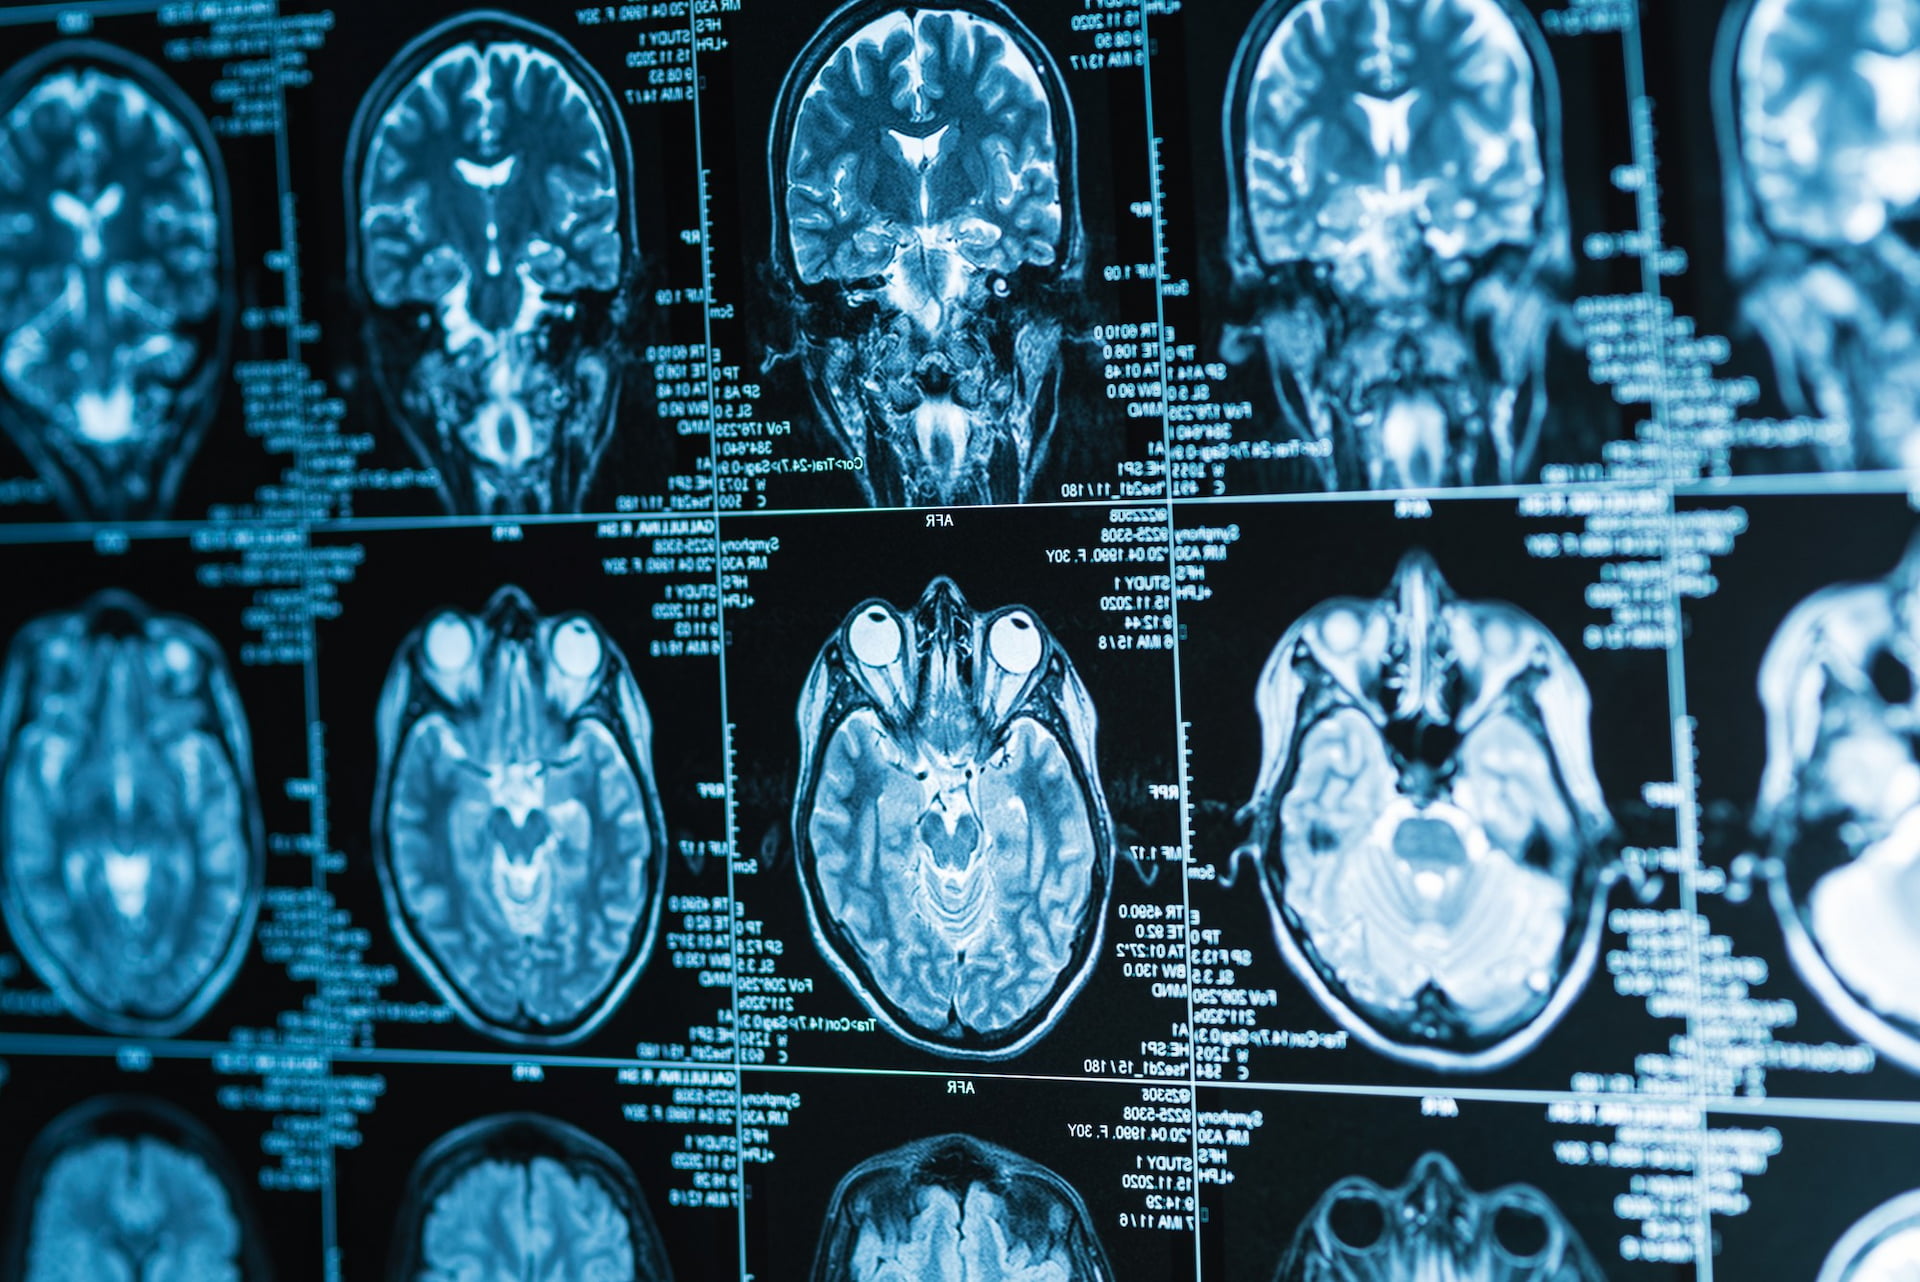

В медицинском диагностическом центре «МРТ Стандарт» вы можете пройти комплексное МРТ головного мозга и придаточных пазух носа в Уфе на высокоточной аппаратуре экспертного уровня.

Головные боли, чувство давления в лицевой зоне, заложенность носа и ухудшение самочувствия требуют точной визуализации нескольких анатомических областей одновременно. В медицинском диагностическом центре «МРТ-Стандарт» в Уфе вы можете пройти МРТ головы и носовых пазух на современном оборудовании и получить заключение в день обращения.

• МРТ головного мозга — метод позволяет оценить структуру мозговых тканей, состояние серого и белого вещества, желудочковую систему и прилегающие анатомические зоны. Томография выявляет очаговые изменения, признаки сосудистых нарушений и другие патологические процессы, которые могут вызывать неврологические симптомы.

• МРТ придаточных пазух носа — исследование направлено на визуализацию околоносовых полостей и окружающих мягких тканей. Оценивается состояние слизистой оболочки, наличие воспалительных изменений, уровень жидкости, анатомические особенности строения. МРТ используется, чтобы уточнить характер процесса в придаточных структурах и определить его распространённость.

В медицинском диагностическом центре «МРТ-Стандарт» обследование выполняется с применением современных магнитных томографов, что обеспечивает высокую точность визуализации мягких тканей. Вы можете выбрать удобное время и пройти МРТ головы и носовых пазух в комфортных условиях.